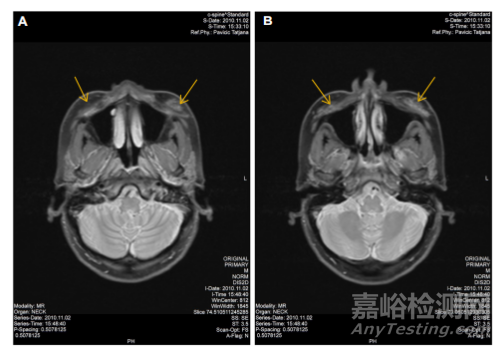

注射CaHA后立即拍攝的MRI圖像顯示,填充劑在骨膜上平面呈對(duì)稱分布(圖 4)。注射約 2.5年后拍攝的圖像顯示未檢測(cè)到 CaHA,表明所有注入的材料已被吸收, 從而證實(shí)了該產(chǎn)品的可生物降解特性(圖5)。如圖5所示,MRI檢查未發(fā)現(xiàn)局部軟組織水腫、不對(duì)稱或病理性增大的區(qū)域淋巴結(jié)。眼眶兩側(cè)的MRI檢查結(jié)果均無(wú)異常,沒(méi)有眶旁或球后浸潤(rùn)或腫塊的證據(jù)。自注射以來(lái)的2.5年內(nèi)未報(bào)告任何并發(fā)癥。

▲圖5

圖5 不含CaHa的相應(yīng)面頰區(qū)域的水平剖面。注:(A,B)MRI圖像是在注射CaHa后約2.5年用Magnetom skyra3.0獲得的圖像。在任何相應(yīng)的MRI切片中未檢測(cè)到CaHA。